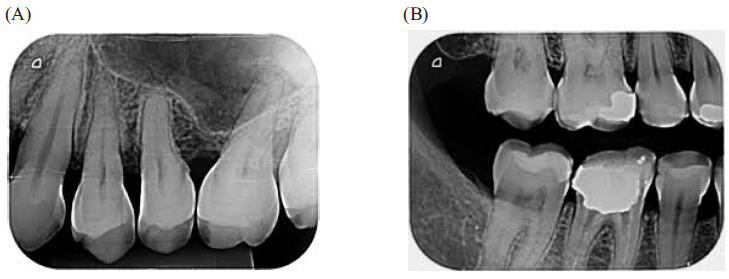

Identifique, nas imagens, os tipos de radiografias intraorais:

Fonte: Google imagens